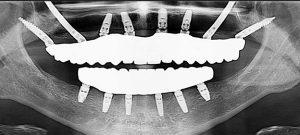

در روش های معمول کاشت ایمپلنت های زیگوماتیک، یک ایمپلنت در هر طرف فک بالا قرار می گیرد. این ایمپلنت ها را می توان با ایمپلنت های دندانی سنتی در ناحیه جلوی فک ترکیب کرد، مشروط بر اینکه استخوان کافی در دسترس باشد. این توزیع به متعادل کردن نیروهای بایت کمک می کند و پشتیبانی بهینه ای برای دندان های ثابت فراهم می کند.

همچنین در شدیدترین موارد تحلیل استخوان، ایمپلنت های چهارتایی زیگوماتیک ارائه داده می شوند. معمولاً این بیماران مدت طولانی بدون دندان بوده اند. با ایمپلنت های چهارتایی زیگوماتیک، به جای دو ایمپلنت زیگوماتیک، چهار ایمپلنت زیگوماتیک در هر فک قرار داده می شود.

توجه داشته باشید ارتفاع مناسب برای قرار گیری پایه ایمپلنت در داخل فک حدود ۱۰ میلی متر است. در صورت ناکافی بودن تراکم استخوان، روش های سینوس لیفت یا پیوند استخوان نیز مورد استفاده قرار می گیرند که به دلیل عوارض زیادی که دارند و همینطور طولانی شدن مدت درمان، زیاد توصیه نمی شوند. به طور کلی استفاده از ایمپلنت های زیگوماتیک برای بیمارانی با دندان های شکسته و دندان های لق دارند و افرادی که تحت عمل های جراحی زیادی قرار گرفته اند، روش درمانی مناسبی گزارش شده است. ایمپلنت های زیگوماتیک معمولی، هنگامی که (در صورت امکان) در ناحیه جلوی دهان با ایمپلنت های سنتی ترکیب شوند، می توانند به طور مؤثر فک بالا را بازسازی کرده و کیفیت زندگی بیماران را بهبود بخشند. این ایمپلنت ها با اتصال به استخوان متراکم زیگوماتیک، می توانند به ثبات عالی دست یابند و از یک بریج ایمپلنت ثابت پشتیبانی کنند و هم عملکرد و هم زیبایی را احیاء کنند.